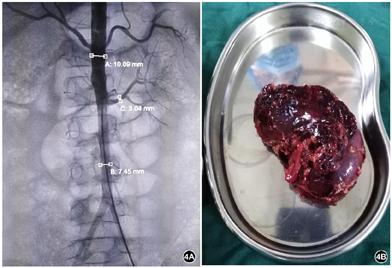

入院前外院检查:64排主动脉全程CTA:降主动脉近端局限缩窄;心脏彩超:主动脉缩窄,二尖瓣低回声赘生物(炎性?);血培养:金黄色葡萄球菌,红霉素耐药,对所有大环内酯类抗生素交叉耐药。入院后检查:血常规:WBC 10.79×109/L,RBC 3.44×1012/L,Hb 86 g/L,Plt 213×109/L,N 84.0%,L 11.0%,CRP 82.51 mg/L;G试验及GM试验阴性;细菌毒素动态定量检测<5 pg/ml;PCT、淋巴细胞亚群测定及免疫球蛋白正常;ESR、ASO、自身抗体谱、风湿六项、ANCA全套均正常;脑脊液常规、生化、培养正常;血培养、骨髓培养均为:金黄色葡萄球菌,对青霉素耐药,对苯唑西林、万古霉素、利奈唑胺等敏感;心脏超声:心脏各房室内径正常,未见明显赘生物,主动脉弓降部自左锁骨下动脉发出约26.0 mm处内径变窄,较窄处内径约2.9 mm,降主动脉远端前向血流4.59 m/s;胸部及腹部CT平扫(图1):左肺门及左后纵隔团片状软组织密度影;双肾大小、形态可,未见明显异常密度影。

入院后予万古霉素、美罗培南抗感染及支持对症治疗,仍有发热,体温波动于38℃左右,于住院第5天偶诉胸痛、胸闷,可耐受,可自行缓解,复查心脏超声:肺动脉分叉处与降主动脉间见一囊实性回声包块,显示范围约74.8 mm×55.9 mm,内为等回声及无回声。于住院第6天胸痛、胸闷症状加重,伴多汗,每次持续1~20 min不等,前倾位稍缓解,伴呼吸、心率增快,发作时监测血压明显增高,收缩压最高达170 mmHg,含服硝苯地平后可暂时缓解。查体:精神反应欠佳,面色稍苍白,呼吸频率33次/分,三凹征阴性,双肺呼吸音粗,左肺呼吸音减低,可闻及少许痰鸣音,心率101次/分,心音有力,律齐,腋前线第4肋间可闻及2/6级收缩期杂音,足背动脉搏动弱,余未见明显阳性体征。行纵隔增强CT(图2):降主动脉起始段明显缩窄,直径约2.3 mm,狭窄段远端约17 mm处可见降主动脉前缘一膨大造影剂影突出腔外,最大截面约4 5mm×31 mm,上下长度约32 mm,主动脉裂口处宽度约19.4 mm,突出部分周围可见环状软组织密度影包绕,考虑假性动脉瘤形成;复查血常规:WBC 16.17×109/L,Hb 92 g/L,HCT 28.20%,Plt 357×109/L,N 87.0%,L 8.2%,CRP 69.11 mg/L。完善术前检查,于住院第9天全麻低温体外循环下行降主动脉瘤切除、主动脉缩窄切除、人工血管置换术、肺脓肿引流术。术中探查见主动脉峡部缩窄,内径0.3 cm,长约1.2 cm,缩窄段以远2.0 cm处起始主动脉破口,长约3.0 cm,横径1.5 cm,瘤体深入至左肺叶内,5.0 cm×6.0 cm×6.0 cm大小,左肺整体不张实变,张力较高。术中诊断:主动脉缩窄、降主动脉假性动脉瘤、感染性心内膜炎、肺炎并肺脓肿。病理检查示:壁内纤维组织增生及片状出血伴炎症反应,符合假性动脉瘤。术后呼吸机辅助通气,继续予美罗培南+万古霉素抗感染、硝普钠控制血压,体温正常,病情逐渐恢复。于住院第18天,患儿偶诉腹痛,可自行缓解,伴有低热,37.4℃,当天夜间,患儿突然腹痛加重,伴面色苍白、烦躁、意识淡漠。体格检查:T 37.4℃,P 120次/min,R 40次/min,BP右上肢110/65 mmHg。意识模糊,面色及口唇苍白,颈软,无抵抗,呼吸稍促,三凹征阴性,双肺呼吸音粗,未闻及明显湿啰音,心率120次/min,心音有力,律齐。腹韧,右下腹压痛、反跳痛及肌紧张,肝脾肋下未触及,肠鸣音正常,四肢末梢凉,CRT 4 s。急查腹部超声示:右腹部异常回声包块(血肿形成?),急诊腹部增强CT(图3):右肾动脉近段纤细,远端未见显示,右肾实质内可见数条纤细较淡造影剂血管影走行,右肾静脉未见明确显示。右肾受压右移,其内侧及下缘周围可见大片状不均质密度影,大小约90 mm×88 mm×121 mm,内部密度不均,未见明显强化,考虑为巨大血肿。立即全麻下行多学科联合手术(心内科、心外科、普外科、泌尿外科),行腹主动脉造影+肾动脉球囊扩张术+单侧肾切除术+腹膜后血肿清除术。行腹主动脉造影示右肾动脉造影剂外溢。右腹部脐上2 cm长约18 cm横切口,依次打开皮下、腹直肌、腹膜,见腹腔大量凝血块、不凝积血,右下腹膜外巨大血肿,肝脏受压,肠道移向右腹部,右肾呈暗红色,已失活,肾动脉不规则破裂达2/3直径。球囊充液扩张阻断腹主动脉近右肾动脉开口处血流(图4)。清除腹腔及腹膜外凝血块、积血等,暴露肾蒂,游离右肾动静脉、输尿管,7#丝线分别双重结扎、切断右肾动静脉,回抽球囊开放血流,未见出血。同时结扎、切断右侧输尿管,取出失活右肾(图4),充分止血,盐水2000 ml冲洗腹腔。术中诊断:肾动脉破裂;腹膜后血肿。病理诊断:右侧肾脏广泛出血、坏死(图5)。术后体温不稳定,血压仍高,且转氨酶逐渐升高,于住院第33天将万古霉素更换为利奈唑胺(斯沃),后体温逐渐正常,于住院第63天将抗生素降级为舒普深,3 d后停抗生素,观察2 d无症状,临床治愈,于2018年6月29日出院。